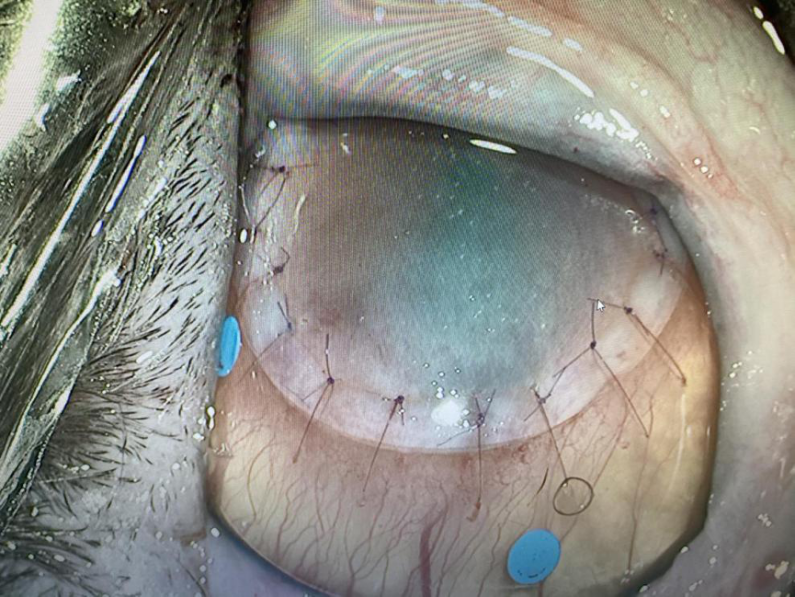

黑色角膜坏死腐骨案例跟踪

米乐病例分析猫咪坏死性角膜炎角膜腐骨